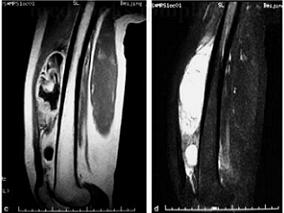

1小时条评论23岁女性患者,主因腰痛5个月,加重伴双下肢麻木无力20 余天,门诊收入院。CT 引导下穿刺活检病理报告为胸11 椎体骨巨细胞瘤。脊柱肿瘤少见,原发性脊柱肿瘤更少见。年龄对于脊柱肿瘤诊断非常重要,您知道这是为什么吗? (1)病例介绍 :患者,女,23岁,主因腰痛...